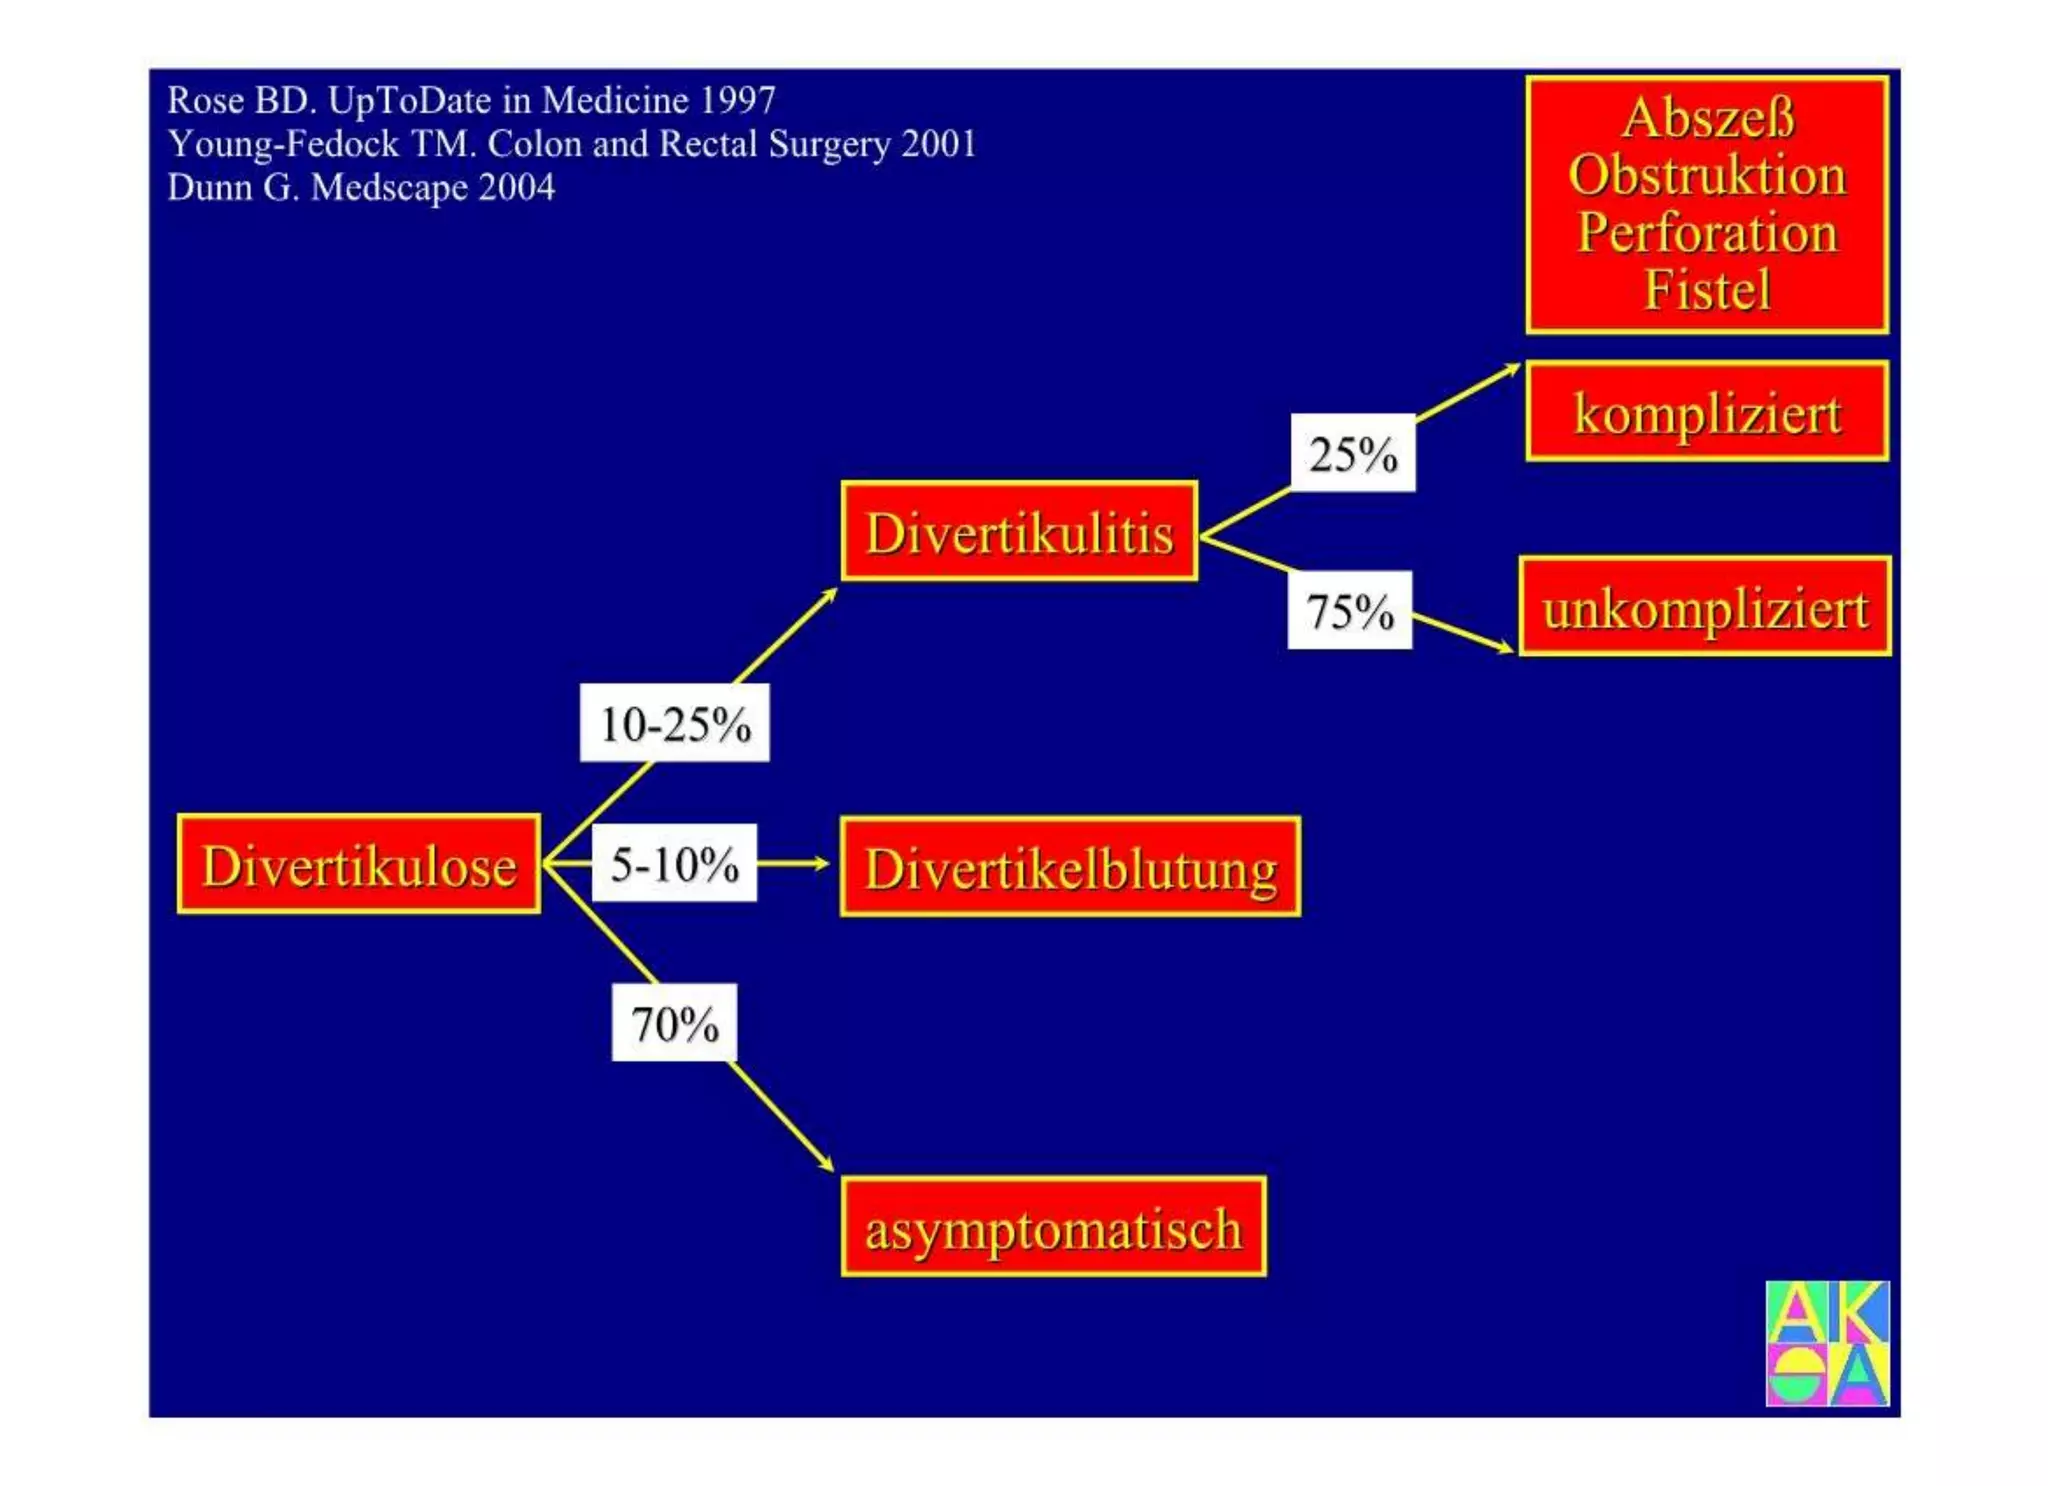

Chronische Enteropathie und Ileus, Dünndarm und Dickdarmdiagnostik, Mechanischer und paralytischer Ileus, Eingeklemmte Darmabschnitte, aufgereihter Bridenileus, und dazu Dickdarmileus, eingeklemmte Hernien, Weitergabeskript